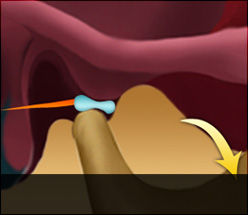

디스크 전방전위1

입을 다물고 있는 상태

입을 열고 있는 상태

입을 열면 디스크가 제자리로

돌아가는 경우